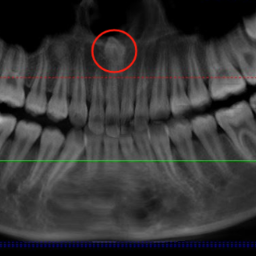

小成颌骨内埋伏着一颗多生牙。

红网时刻新闻7月10日讯(通讯员 唐宇扬 余顺)长沙13岁的小成(化名)因牙齿排列不齐准备接受正畸治疗,却在拍牙片时意外发现其上颌骨内埋伏着一颗多生牙,位置紧贴鼻底。近日,湖南省人民医院口腔二病区徐裕国主任医师为其实施经鼻腔入路微创拔除上颌埋伏多生牙手术,以微创技术破解了传统拔牙创伤大、损伤邻牙的难题,为孩子的牙颌健康保驾护航。

“没想到牙齿还能长到这里。”小成妈妈介绍,孩子在一次口腔检查中发现牙齿排列不齐,于是趁着暑假有时间来口腔二病区做正畸,却偶然发现了这颗埋伏的多生牙。徐裕国主任医师团队考虑,这颗牙若采用常规口内入路拔除,需磨除大量唇侧骨板,不仅创伤大、恢复慢,还可能损伤邻牙牙根,影响后续矫正效果,而孩子年龄小,正处于骨骼发育关键期,于是决定另辟蹊径——从鼻腔内微创入路拔牙。